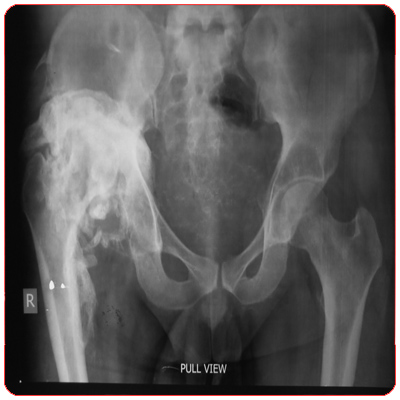

![]() Rheumatoid arthritis with destroyed hip joints (clickimage for enlarge view) | ![]() Bilateral Uncemented Total Hip Replacement (clickimage for enlarge view) |